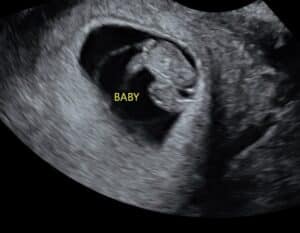

Reversing A Burned Tubal Ligation: Our Little Miracle Is Growing!

Our little miracle is growing healthy and beautifully. We can’t wait to meet him June of 2025.

Patient age: 36

Tubal ligation type: Coagulation (burned)

Patient hometown: Blaine, Minnesota